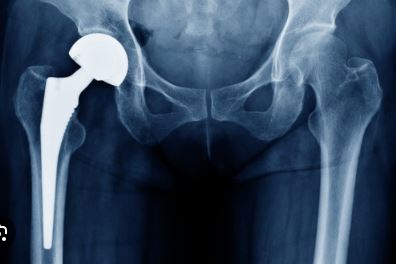

The further advancement is that now we are using ceramic heads wherein the ceramic ball bearing surface’s life is much more than the conventional implants. With a hip replacement, young people are getting a new lease of life. They are able to do their activities and enjoy their life. The components of a hip replacement are a socket which fits into the pelvis, a stem that fits into the thigh bone known as femur and connecting both of them is a head. The head is very important as it is now ceramic instead of metal. The skill of the surgeon is to give a perfect fitting socket as well as femoral stem so that patients can start working from day one. They don’t have to go for bed rest for 2-3 months as earlier was the case. So now with MIS technique, we are able to allow these patients to sit on the ground, sit cross-legged and use Indian toilets.